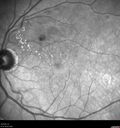

Macular ischemia left eye in type I diabetic (enlarged foveal avascular zone)213 views29 year old female with type I diabetes since age 5. Left eye has enlarged FAZ with vision of 20/20 OD and 20/60 OS. Both eyes have CSME. The left eye did have focal laserApr 12, 2023